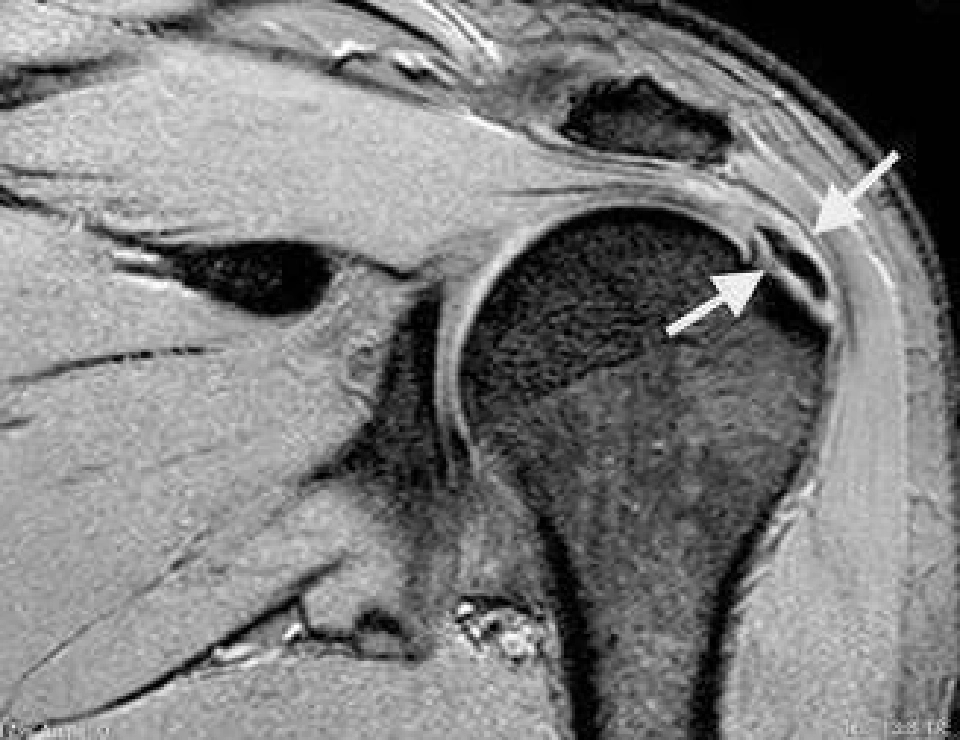

การรักษาเริ่มแรก แพทย์จะทำการวินิจฉัยโรคจากอาการ การซักประวัติและตรวจร่างกาย ร่วมกับการตรวจแบบอื่นเพื่อยืนยันการวินิจฉัย เช่น ตรวจเอกซเรย์เพื่อดูความผิดปกติของกระดูก หรือตรวจ MRI เพื่อวินิจฉัยภาวะเสื่อมหรือการขาดของเส้นเอ็นบริเวณไหล่ และยังสามารถให้รายละเอียดของกระดูกอ่อนและเนื้อเยื่อรอบข้อไหล่ได้ดี โดยแบ่งการรักษาออกเป็น 2 รูปแบบใหญ่ๆ คือ 1.ไม่ต้องผ่าตัด สำหรับกรณีที่ผู้ป่วยมีกระดูกงอกทับเอ็นข้อไหล่ในระยะเริ่มต้น และไม่มีอาการของข้อไหล่ฉีกขาดร่วมด้วย โดยจะใช้วิธีทานยา ฉีดยา หรือทำกายภาพบำบัด ร่วมกับลดกิจกรรมที่กระทำต่อข้อไหล่ ออกกำลังกายเพื่อป้องกันภาวะกล้ามเนื้อฝ่อตัวจากการไม่ได้ใช้งาน บางรายใช้เวลาในการรักษาไม่นาน บางรายรักษาไม่หายทนทรมานต่อความเจ็บปวด หากทำทุกวิธีแล้วยังไม่ดีขึ้นอาจต้องเข้ารับการผ่าตัด